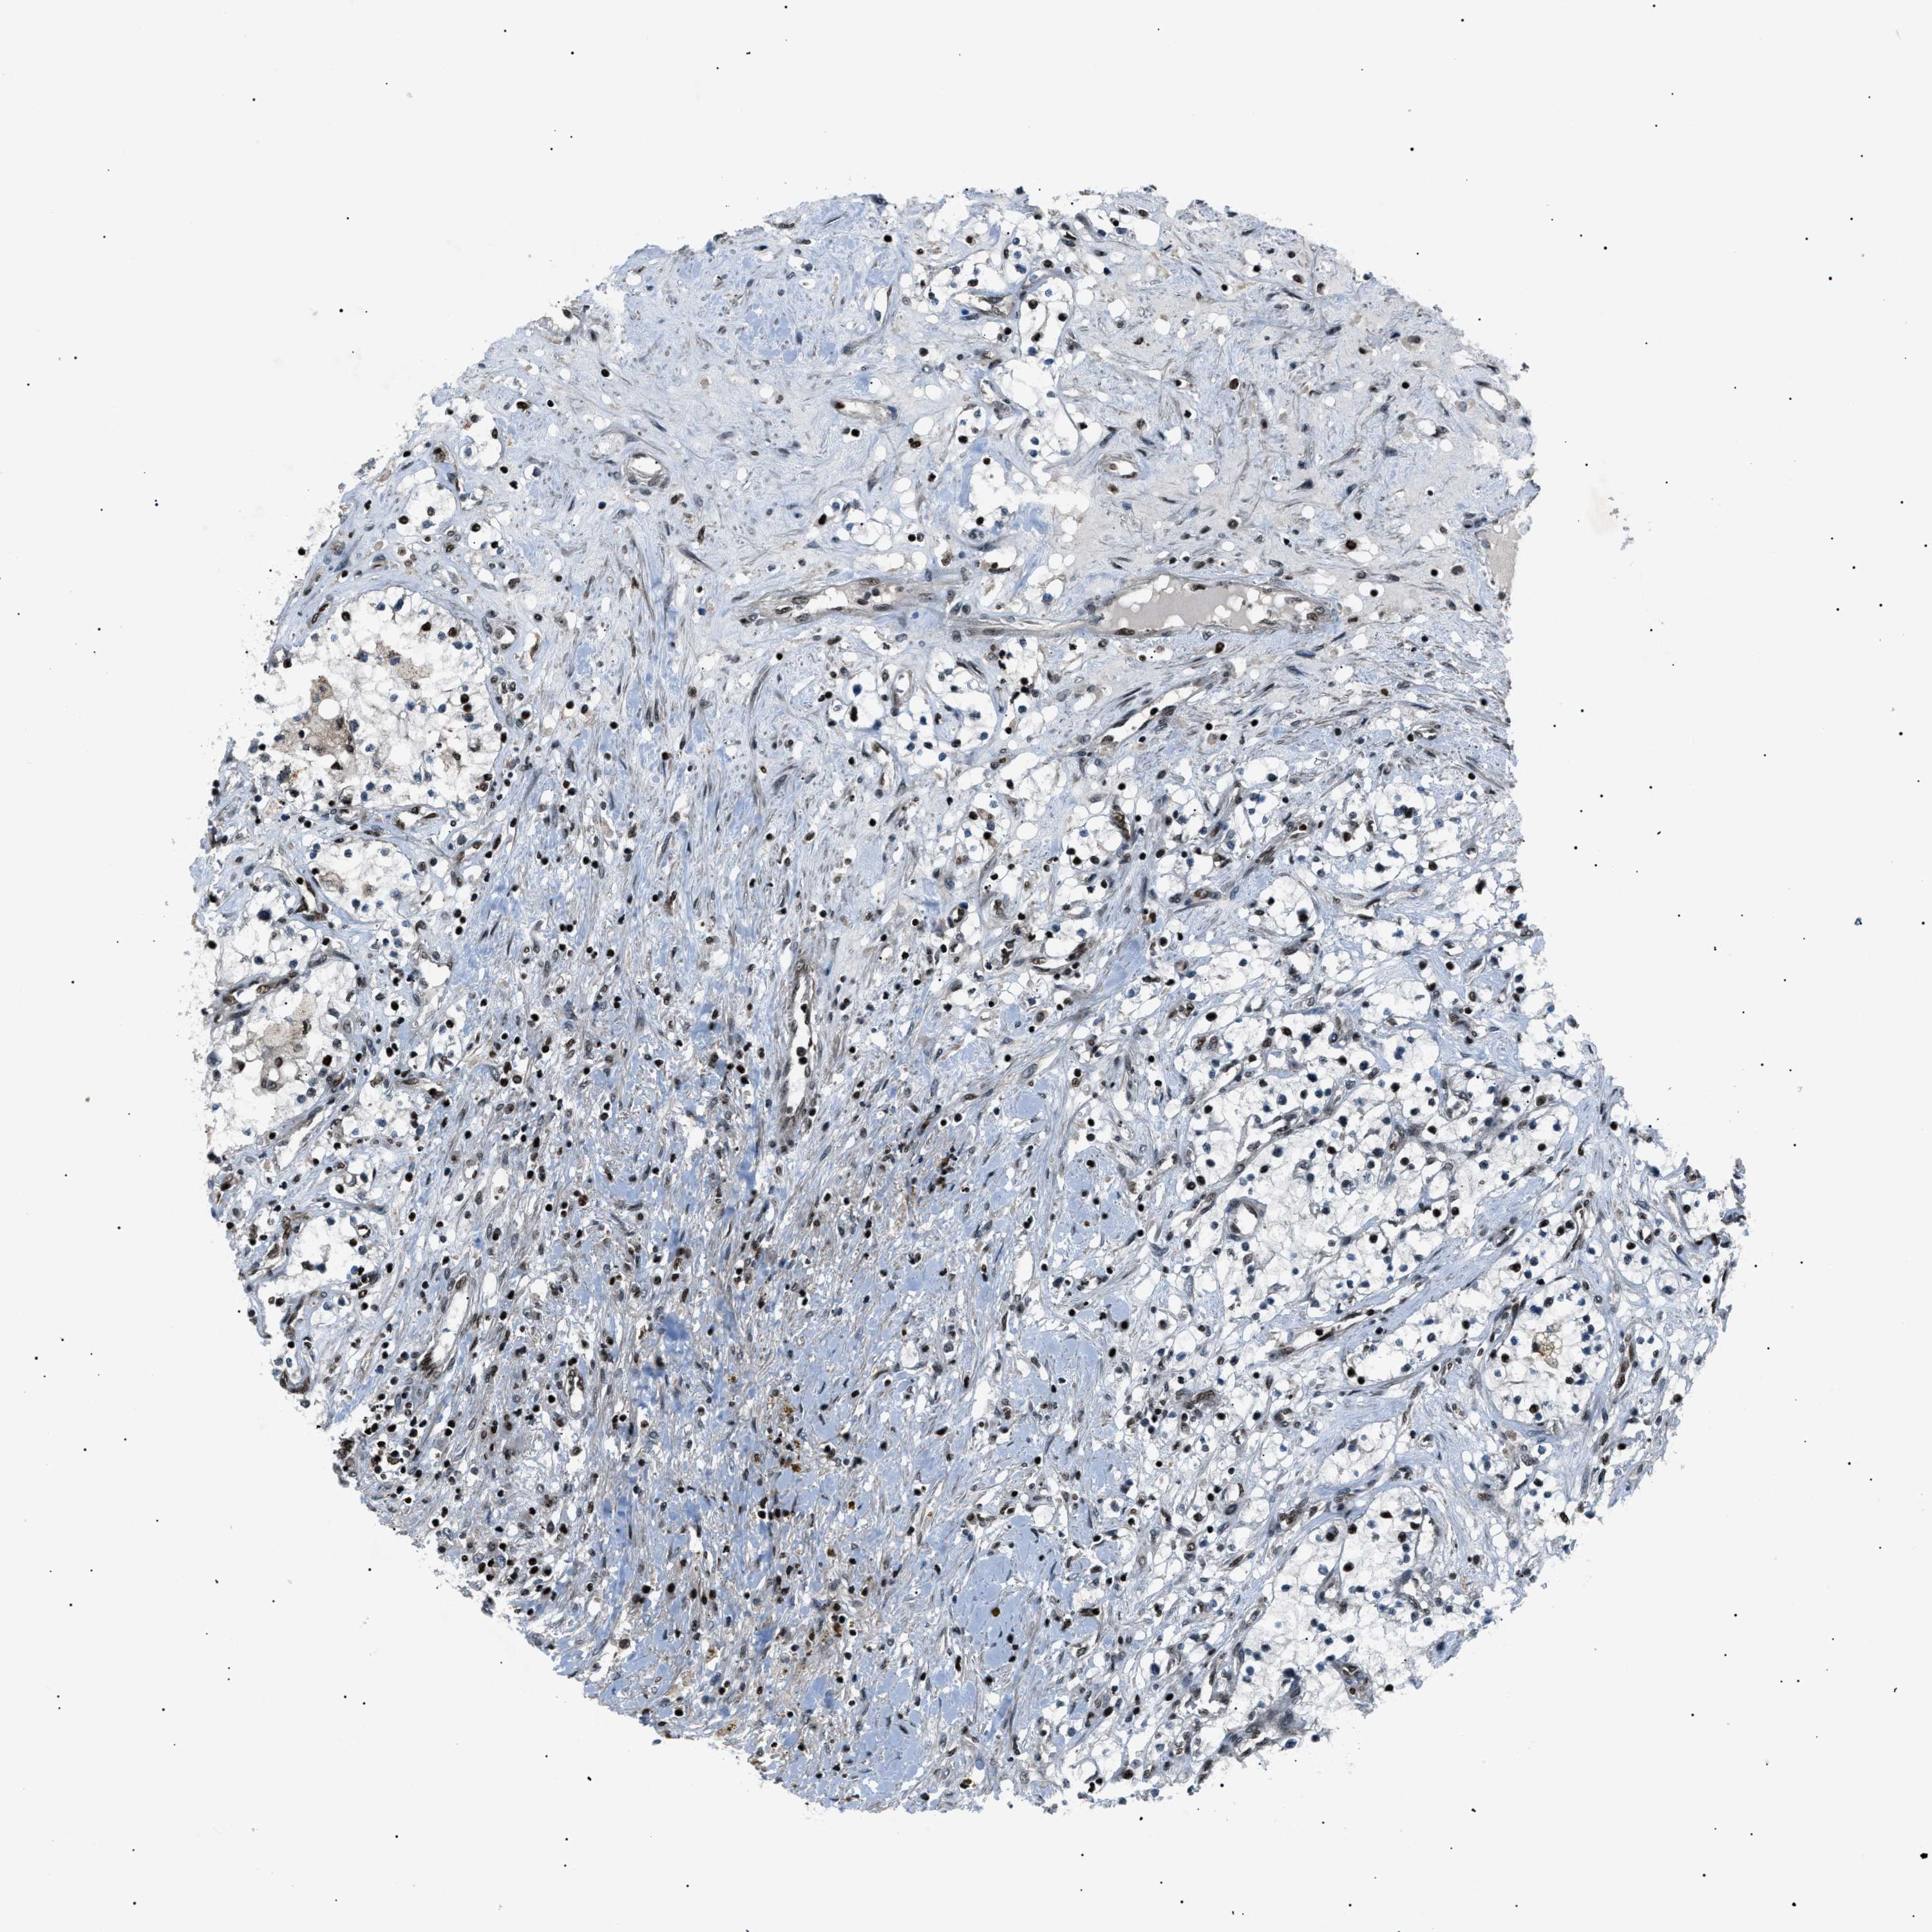

CANCER RENAL CANCER Show tissue menu

KICH TCGA KIRC TCGA KIRC VALIDATION KIRP TCGA PROTEIN RCC CPTAC PROTEIN EXPRESSION

KIDNEY CHROMOPHOBE (TCGA) - Interactive survival scatter ploti

The Survival Scatter plot shows the clinical status (i.e. dead or alive) for all individuals in the patient cohort, based on the same data that underlies the corresponding Kaplan-Meier plots. Patients that are alive at last time for follow-up are shown in blue and patients who have died during the study are shown in red.

The x-axis shows the expression levels (FPKM) of the investigated gene in the tumor tissue at the time of diagnosis. The y-axis shows the follow-up time after diagnosis (years). Both axes are complimented with kernel density curves demonstrating the data density over the axes. The top density plot shows the expression levels (FPKM) distribution among dead (red) and alive patients (blue). The right density plot shows the data density of the survived years of dead patients with high and low expression levels respectively, stratified using the cutoff indicated by the vertical dashed line through the Survival Scatter plot. This cutoff is automatically defined based on the FPKM cutoff that minimizes the p-score. The cutoff can be changed by dragging the vertical line or by entering a cutoff value in the square labeled "Current cut-off".

Under the Survival Scatter plot the p-score landscape (black curve; left axis) is shown together with dead median separation (red curve; right axis). Dead median separation is the difference in median mRNA expression between patients who have died with high and low expression, respectively. It is calculated as follows: median FPKM expression of dead patients with high expression - median FPKM expression of dead patients with low expression. This is intended to aid the user in visually exploring custom cutoffs and the associated p-scores and dead median separation.

Individual patient data is displayed and can be filtered by clicking on one or more of the category buttons on the top of the page. Categories describing expression level and patient information include: high, low, alive, dead, female, male and tumor stages. The scale of the x-axis can be toggled between linear and log-scale by clicking on the "x log" button. Mouse-over function shows TCGA ID, patient information and mRNA expression (FPKM) for each patient.

& Survival analysisi

Kaplan-Meier plots summarize results from analysis of correlation between mRNA expression level and patient survival. Patients were divided based on level of expression into one of the two groups "low" (under cut off) or "high" (over cut off). X-axis shows time for survival (years) and y-axis shows the probability of survival, where 1.0 corresponds to 100 percent.

PRKX is not prognostic in Kidney Chromophobe (TCGA)